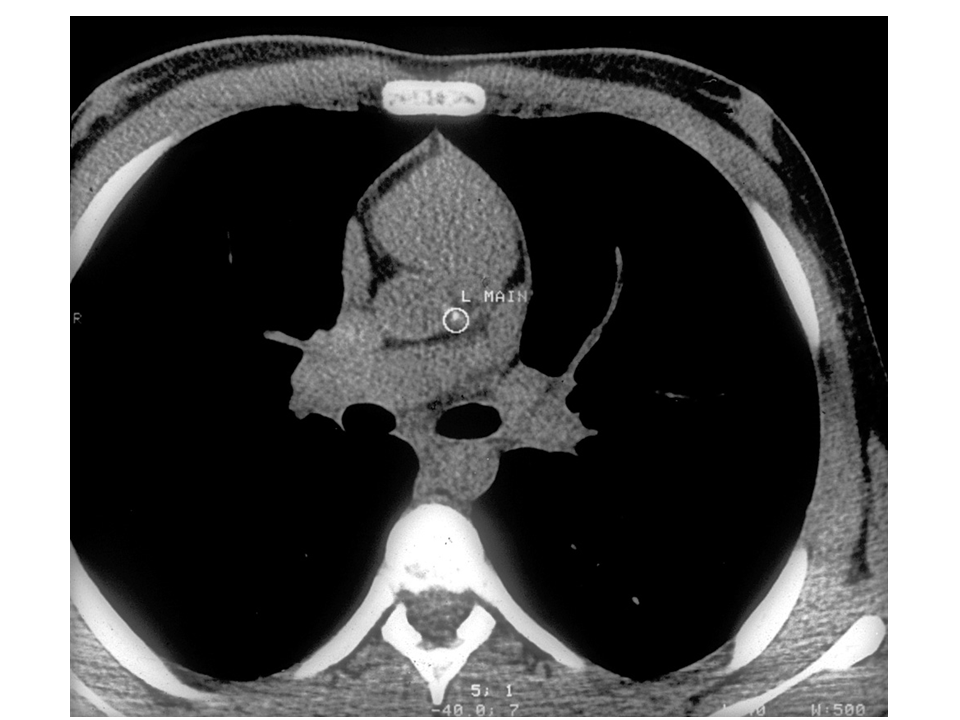

Gidding - Figure 3 - CT calcium scan

This Figure is a computerized tomography (CT) scan of a 14-year old child whose father had FH and had a heart attack at age 27. This particular teenager had a total cholesterol level of 429 mg/dL, an HDL cholesterol level of 27 mg/dL, and as can be seen in the Figure, coronary calcium in the left main coronary artery. In other words, already by the age of 14, this child has evidence of significant atherosclerosis – which serves as an excellent example of the importance of the new FNLA recommendations for recognizing and treating FH in children.

Gidding S. J Clin Lipidol. 2011; 5(6).